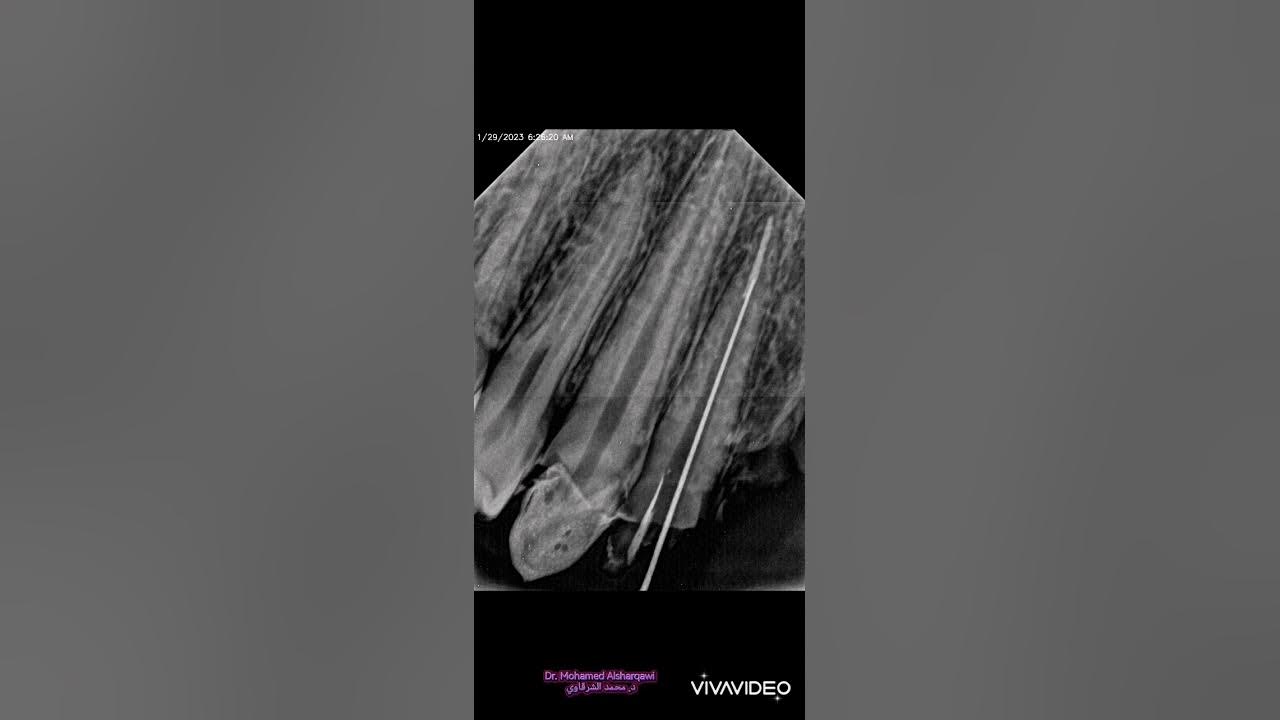

Endodontic treatment reduction for PFM Bridge YouTube Pfm Reduction if approved, pack cord for isolation and determine the amount to prepare subgingivally. pfm crown preparation requires proper tooth reduction to fit both porcelain and metal. Begin preparation (reducing and shaping with a handpiece). margin junction (interproxima) follows the anatomical contour of the margin of gingiva. pfm crown prep requires reducing the tooth surfaces to the. Pfm Reduction.